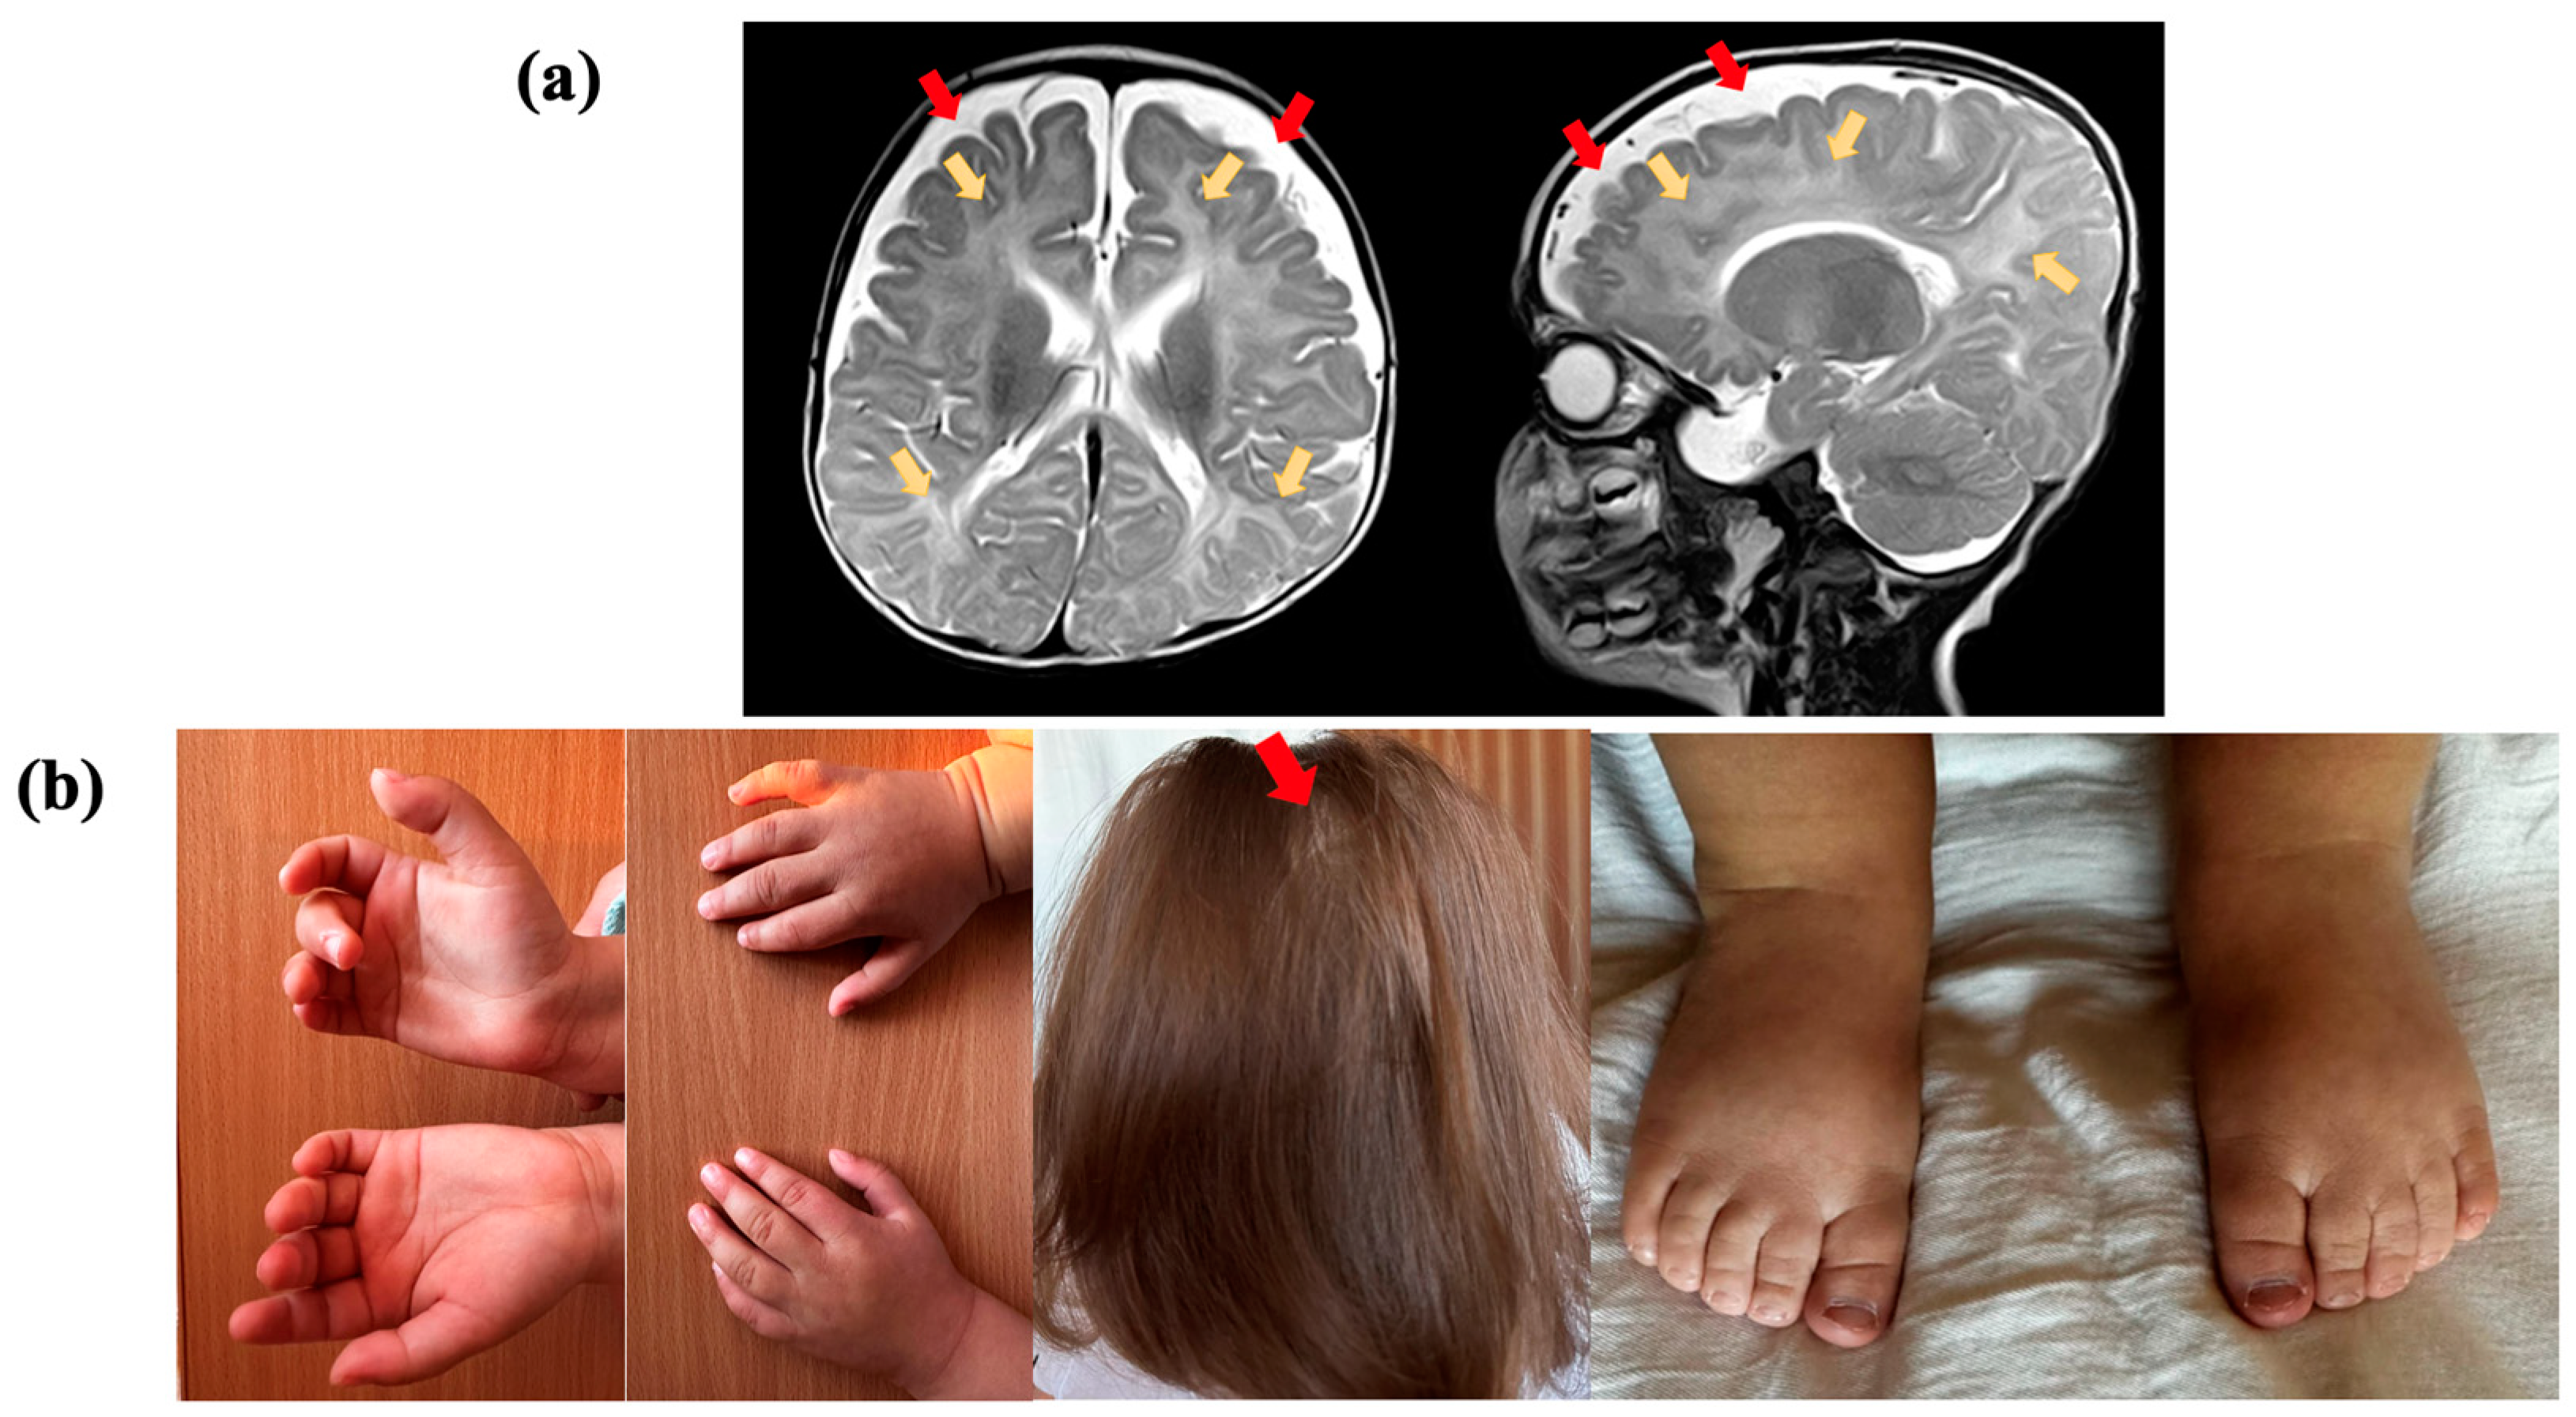

Figure 1.

Clinical presentation of the proband, who had a variant in the TRA2B gene: (a) Brain magnetic resonance imaging (MRI) of the proband at the age of 5 months, in T2-weighted sequence, reveals abnormal paraventricular and subcortical white matter signals (yellow arrows) and the accumulation of cerebrospinal fluid over the frontotemporal areas (red arrows); (b) proband showing cutaneous syndactyly of the 2nd and 3rd toes, clinodactyly of the 5th finger, and alopecia areata.

Electroencephalogram (EEG) results indicated hypsarrhythmia. Brain MRI of the proband at the age of five months, in a T2-weighted sequence, revealed abnormal paraventricular and subcortical white matter signals and an accumulation of cerebrospinal fluid over the frontotemporal areas. The volume and shape of the cerebral ventricles were within the normal range (Figure 1a). Cardiac malformations included patent foramen ovale and a mild stenosis of the left pulmonary artery. No feeding difficulties or sleep disturbances were reported, while information about digestive and vision problems was not provided. The individual had some skeletal anomalies, including cutaneous syndactyly (fusion) of the second and third toes and clinodactyly of the fifth finger. Additionally, the patient had nonspecific facial anomalies such as a high forehead, low-set ears with protruding lower edges, macrostomia, and macroglossia. Alopecia areata was also observed (Figure 1b).